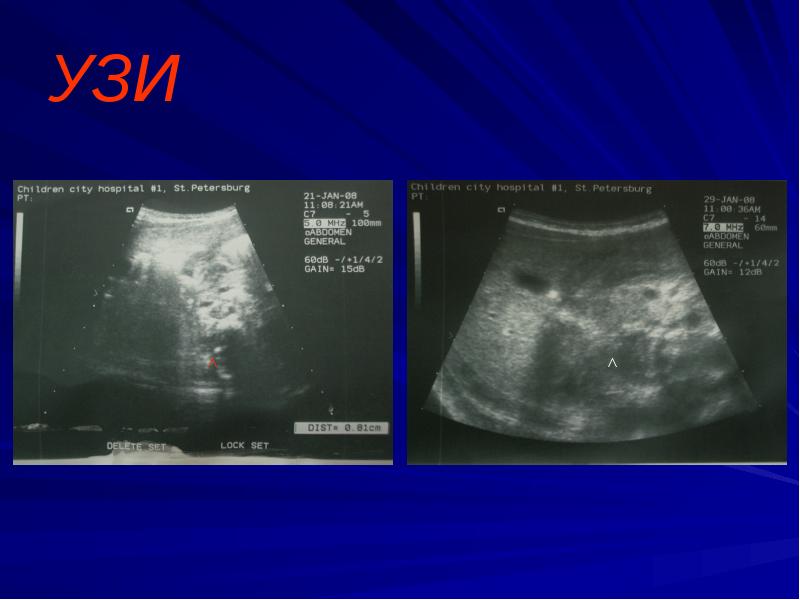

- 6. Диагностика УЗИ желудка - сужение просвета пилорического канала, утолщение мышечной стенки

- 7. УЗИ